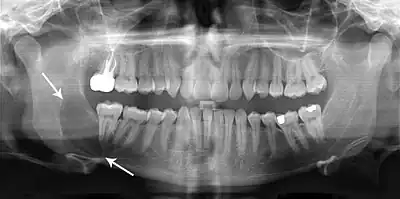

Large odontogenic keratocyst with impacted wisdom teeth superficial to lesion

Diagnosis is usually radiological. However, definitive diagnosis is through biopsy. Aspirational biopsy of odontogenic keratocysts contains a greasy fluid which is pale in colour and contains keratotic squames.[12][2] Protein content of cyst fluid below 4g% is diagnostic of odontogenic keratocysts.[2] Smaller and unilocular lesions resembling other types of cysts may require a biopsy to confirm the diagnosis.[9] On a CT scan, the radiodensity of a keratocystic odontogenic tumour is about 30 Hounsfield units, which is about the same as ameloblastomas. However, ameloblastomas show more bone expansion and seldom show high density areas.[13]

Radiographs of odontogenic keratocysts show well-defined radiolucent areas with rounded or scalloped margins which are well demarcated.[12] These areas can be multilocular or unilocular. The growth pattern of the lesion is very characteristic from which a diagnosis can be made as there is growth and spread both forward and backward along the medullary cavity with little expansion. No resorption of teeth or inferior dental canal and minimal displacement of teeth is seen. Due to lack of expansion of the odontogenic keratocyst, the lesion can be very large when radiographically discovered.[9]